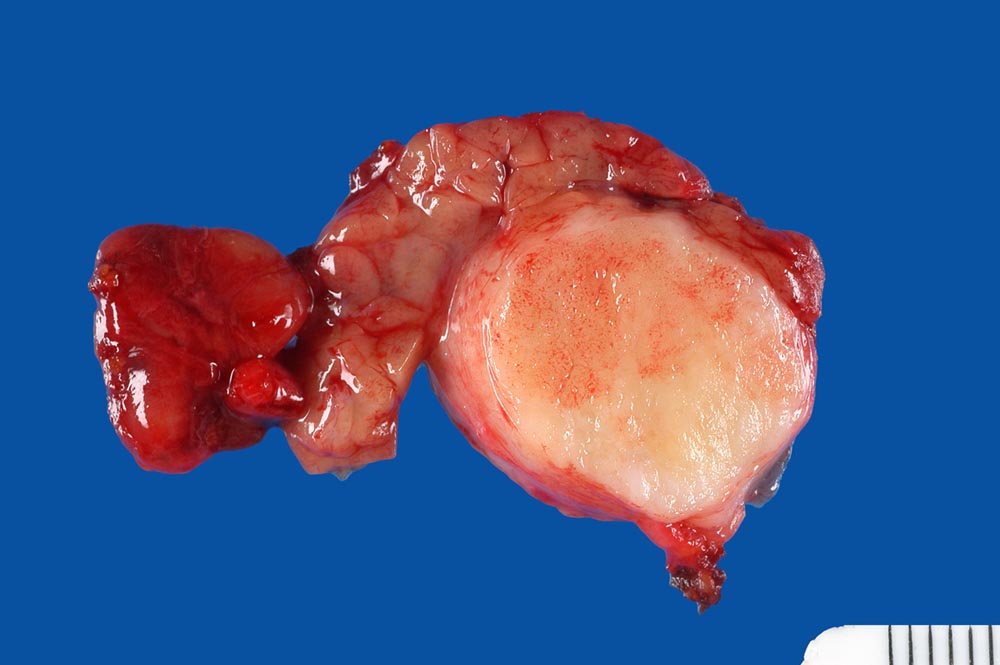

Pleomorphes Adenom der Glandula submandibularis

benigner Tumor

Glandula submandibularis

Innerhalb des makroskopisch unauffälligen Speicheldrüsengewebes findet sich ein bekapselter solider weissglänzender Tumor von 2cm Durchmesser.

Pleomorphes Adenom

Verdacht auf Karzinom der Glandula submandibularis

Makroskopie